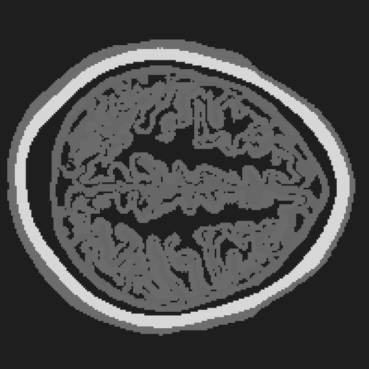

Refer to caption

(a) RCAN.

(b) LDM.

(c) ViT.

(d) BrainPuzzle.

(e) Ground Truth.

(f) RCAN.

(g) LDM.

(h) ViT.

(i) BrainPuzzle.

(j) Ground Truth.

Figure 10: Baseline comparison on partial-array data. Two axial slices: RCAN, LDM, ViT, and BrainPuzzle versus ground truth. BrainPuzzle preserves fine structure and boundary sharpness.

Table II summarizes the average performance over 50 slices of 2D brain images during the testing phase for both the full-transducer and partial-transducer datasets. The results demonstrate that the BrainPuzzle method outperforms all baseline models, achieving the highest SSIM values and the lowest RMSE values in both scenarios. Several key observations can be made: (1) We observe that the U-Net model and super-resolution baselines such as RCAN and CycleGAN achieve inferior performance compared to BrainPuzzle in terms of both SSIM and RMSE. These baseline models are less capable of handling the intricate spatial relationships and texture details required for accurate reconstruction, and thus struggle to effectively recover complete brain images. (2) BrainPuzzle also outperforms more advanced generative models, including LDM and ViT. While LDM and ViT exhibit more complex structures and training processes, they require significantly longer training and inference times compared to BrainPuzzle. Despite their complexity, these models fail to match the accuracy and efficiency achieved by BrainPuzzle, underscoring its robustness and practical applicability. (3) All models demonstrate significantly better performance on the full-transducer dataset compared to the partial-transducer dataset. This superiority is attributed to the clearer and more complete input brain fragments in the full-transducer scenario, which provide essential spatial information and finer-grained textures crucial for accurate reconstruction. In contrast, the partial-transducer data are not sufficient for high-quality reconstruction using limited and fragmented inputs.

The efficacy of the BrainPuzzle method is further demonstrated by the visual results presented in Fig. 10. These results showcase comprehensive brain images reconstructed across multiple 2D slices, highlighting the superior performance of the proposed method. A detailed analysis of these images reveals the following observations: (1) The RCAN baseline exhibits significant limitations in reconstructing the complete structural complexity of brain images. It struggles to capture the fine textures and intricate details characteristic of brain imagery, resulting in noticeably lower-quality reconstructions. (2) BrainPuzzle achieves a significant improvement in image quality, excelling in capturing finer details such as the accuracy of structural contours and the fidelity of textural patterns. These improvements can be particularly critical for medical diagnosis and analysis, where precision and detail play a pivotal role in ensuring reliable outcomes. (3) While LDM and ViT produce reasonably good results, they fall short of BrainPuzzle in accurately reconstructing smaller details. The minor deficiencies in their reconstructions highlight BrainPuzzle’s superior ability to preserve intricate features and deliver higher-quality outputs.